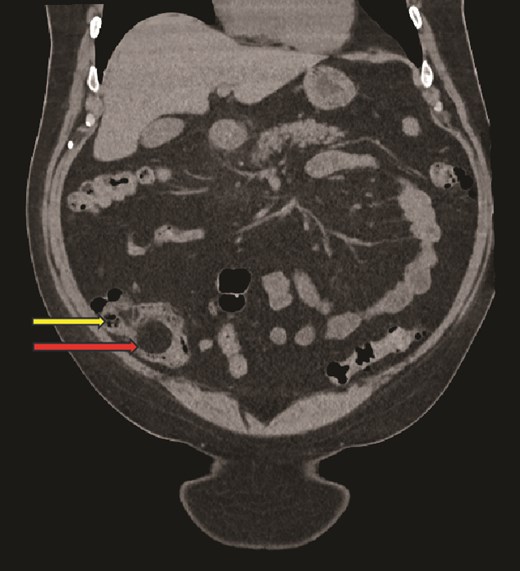

Computed tomography (CT) scan abdomen and pelvis was reported as follows: ‘Inflammatory phlegmon, fat stranding, free fluid, and reactive lymphadenopathy in the right iliac fossa. At the centre of the inflammatory phlegmon there is a dilated appendix with thickened walls. Small appendicolith at the base. Incidental note of a 3.2 cm caecal lipoma, which resides just below the ileocecal valve.’ (Figs 1–3).

Coronal CT image, showing caecal lipoma (superior arrow) and ileo-caecal valve (inferior arrow).